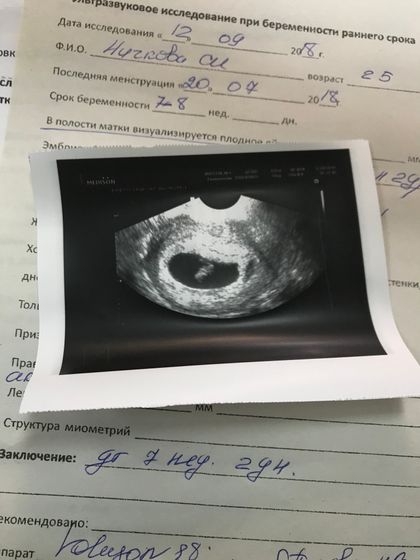

Сегодня произошла наша встреча с малышом? Посмотрели на УЗИ, малыш 11.4 мм, сердечко 140 ударов. Срок 7 недель и два дня???Мы ждём тебя малыш?????????

Это Ктр) и ставят его в миллиметрах)) мы ещё малюсенькие?